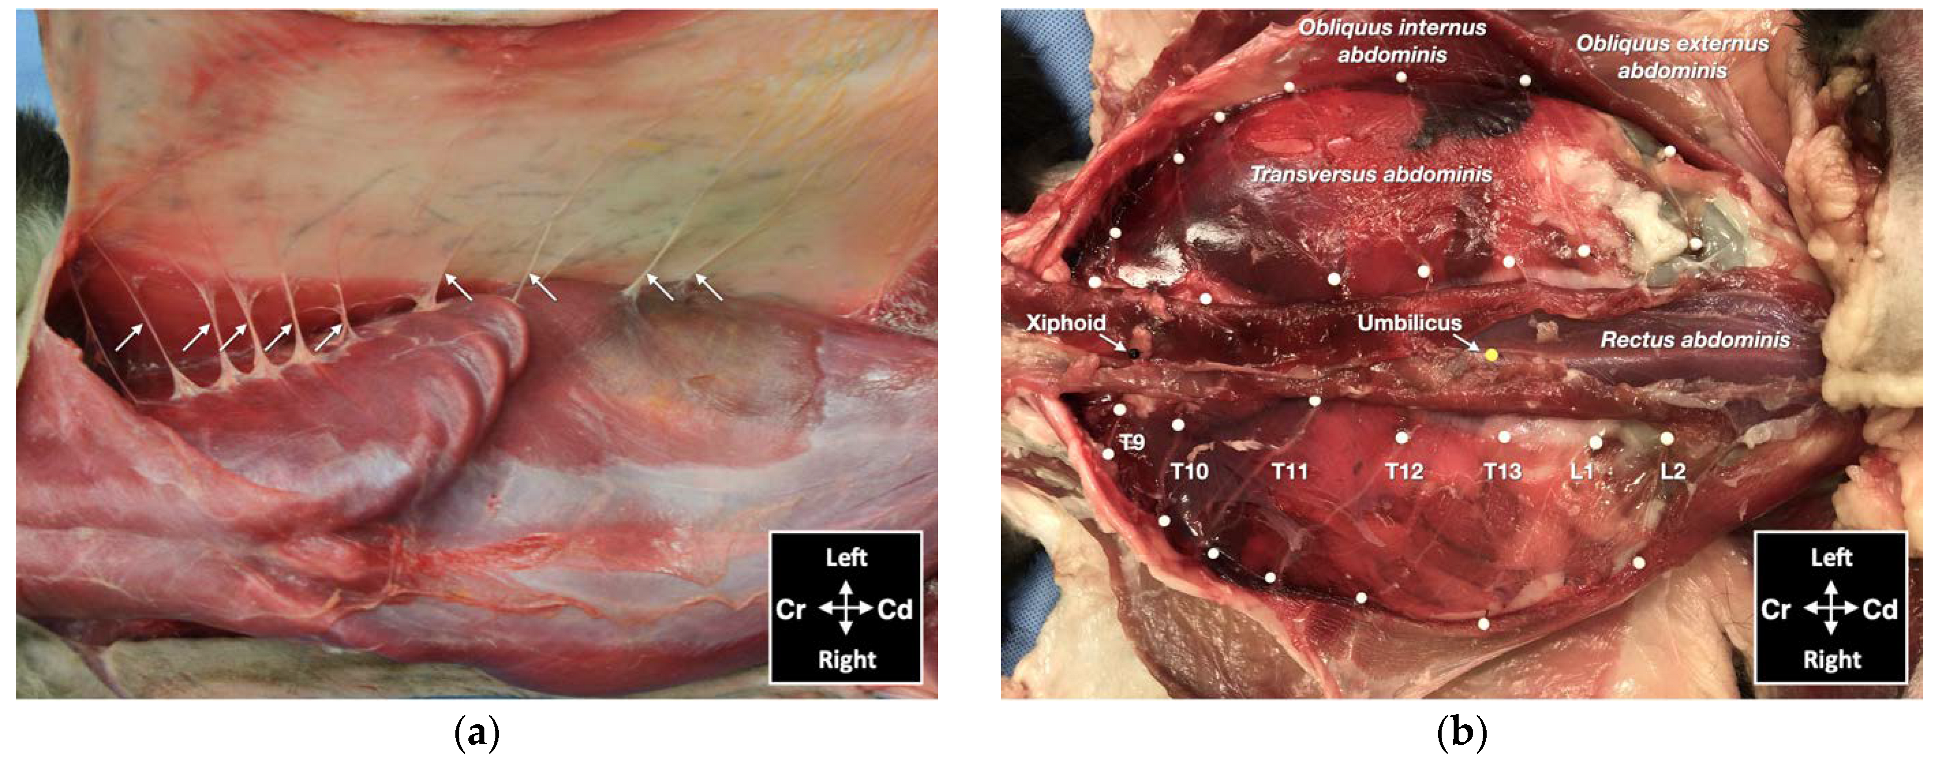

One male and one female cat weighing 4.1 and 3.7 kg, respectively, were studied. The observed anatomy of the abdominal wall musculature and innervation is shown in Figure 4. The belly of the m. transversus abdominis extended through almost the entire abdominal cavity, ended at half of the width of the m. rectus abdominis and extended in a thin aponeurosis to the linea alba. The belly of the m. obliquus internus abdominis, which was found between m. transversus abdominis and the m. obliquus externus abdominis, ended at the mid-width of the hemiabdomen (at about 1 cm lateral to the mammary glands line) and extended in a long aponeurosis to the rectus sheath. The m. obliquus externus abdominis is found along the lateral and ventral part of the abdomen, ending with the most superficial aponeurotic layer of the rectus sheath. Finally, the m. rectus abdominis extended longitudinally in the ventral abdominal wall from the external surface of the thorax to the pubic bone and it is enclosed in the rectus sheath, which multilayered aponeuroses were difficult to dissect. In one cat more than the other, a layer of adipose tissue was observed beneath and immediately caudal the costal arch, between the mm. rectus abdominis and transversus abdominis, extending laterally between the mm. obliquus externus and internus abdominis. The ventral branches of the spinal nerves T9–L3 were identified in both cadavers. These branches were further divided into ventrolateral and ventromedial branches. The ventrolateral branches were located at half of the width of thorax and abdomen (Figure 5a). These branches are found between the intercostal muscles or between the mm. obliquus internus abdominis and obliquus externus abdominis, before they end at the subcutaneous and cutaneous tissues. The ventromedial branches were located within the TAP, with different endings: the T9 branch at the lateral margin of the xiphoid process, T10–L2 at the ventral midline (with T12 and T13 being cranial and caudal to the umbilicus, respectively) and further divided into terminal branches in the belly of m. rectus abdominis, and L3 in the belly of the m. transversus abdominis at the level of the pubis (Figure 5b).

Figure 5. Gross anatomical dissection of two cat cadavers: (a) the lateral cutaneous branches of thoracic (T) and lumbar (L) spinal nerves are indicated by arrows; (b) the ventromedial branches of the spinal nerves from T9 to L2 are indicated by white pins; Cd, caudal; Cr, cranial.